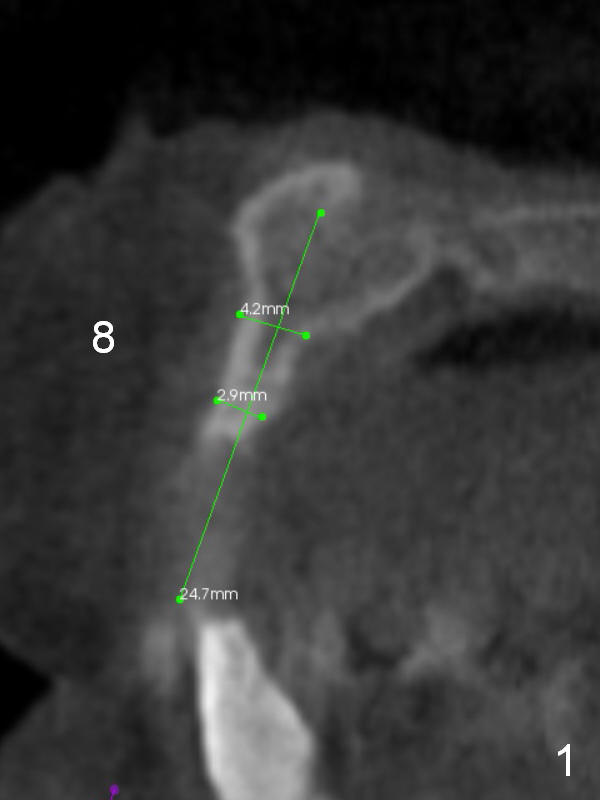

After implant reconstruction of the lower right and left (including #19) regions, the same treatment is considered in the atrophic anterior maxilla (#8-13) for anchorage for upper left molar cross bite correction. The smallest implants are to be placed in the each of the sites with different strategies. For example, at the site of #8 (Fig,1,2), ridge split with wheel (Fig.3) and microsteotomes (Fig.4) are used to place 1-piece implant (3x14 mm). The site of #9 has a pointed ridge and a wide base (Fig.6); a 1-piece angled implant (3x14 mm 15 °) is placed palatally (Fig.7). The ridge and base at #10 are narrow (Fig.8); after truncating the pointed ridge, a 2.0 or 2.5 mm 1-piece implant is placed parallel to the palatal wall (Fig.9).